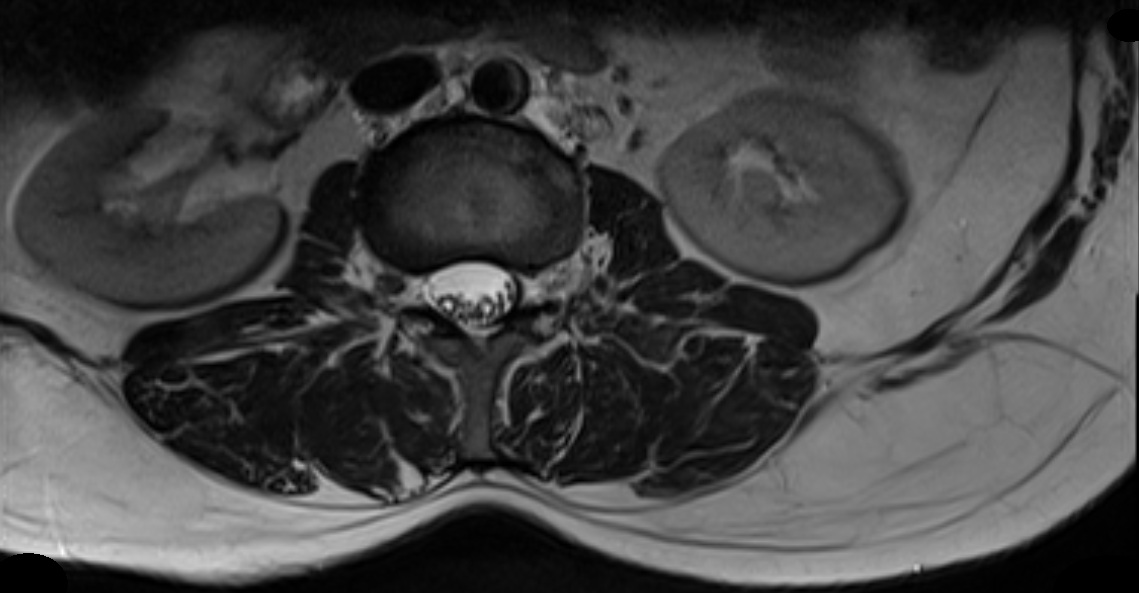

Figure 3: Sequence of original 3D sub-images with missing data for a human spine

Initially, the 2D2𝐷2D slices are split in 4 sub parts as shown in Figure 2 for a human spine, and the data set in divided in two parts. We use single instruction multiple data architecture using 8 logical cores. In parallel, for each block of sub-image, a 3D3𝐷3D matrix is created which is filled with the corresponding data leaving the specified slice gap in between slices as specified for each set as shown in Figure 3. Then edge preserved kriging interpolation is used to generate the 3d subimages. If we want to visualize these sub-images, then we can apply marching cube with color map and visualize the images as shown in Figure 4 and the complete 3D image for visualisation of full spine is as in Figure 5.